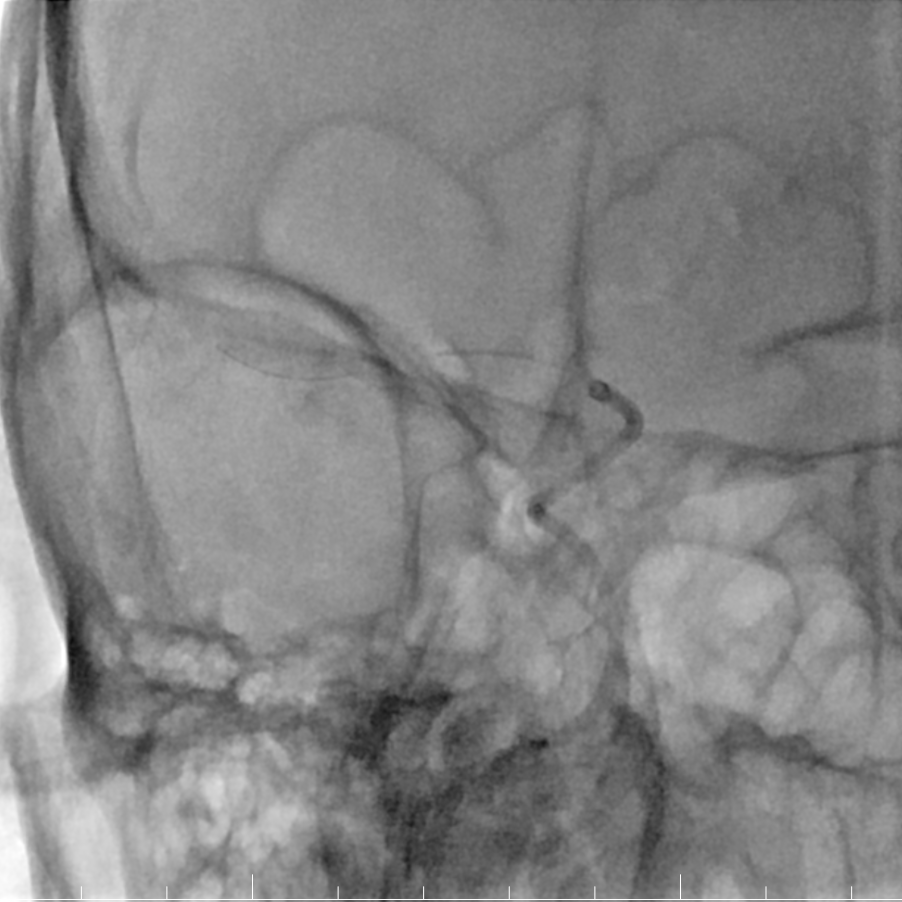

术后影像

术后即刻影像。

动脉长鞘怎么置入有励可说|Locaste 088励楷长鞘及Tarvos微导丝在右侧大脑中动脉M2段取栓术中的应用_https://www.jmylbn.com_新闻资讯_第20张

动脉长鞘怎么置入有励可说|Locaste 088励楷长鞘及Tarvos微导丝在右侧大脑中动脉M2段取栓术中的应用_https://www.jmylbn.com_新闻资讯_第21张

术后复查CT、TCD。